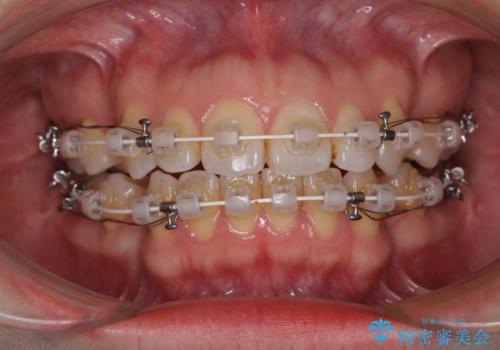

- 矯正装置

- 審美装置

- 唇の閉じにくさを気にして来院された患者様です。

上下左右第一小臼歯4本を抜歯し、ワイヤー装置にて口元を引っ込めるよう矯正治療を行うこととしました。